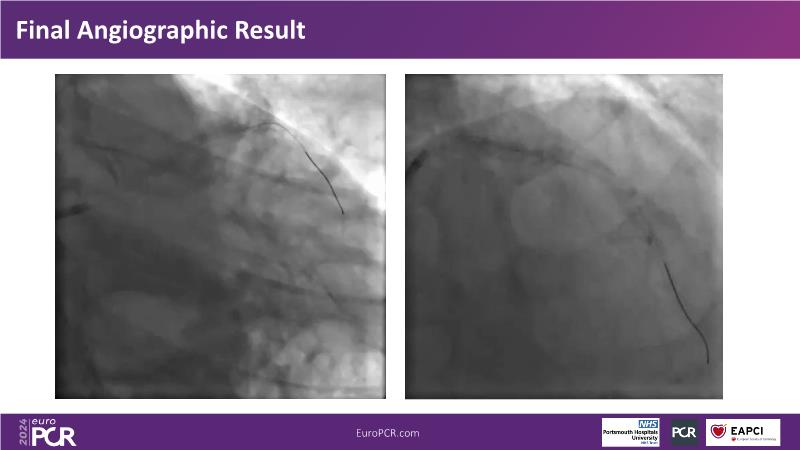

In this session, observe the enhanced user-friendliness of IVUS-guided complex PCI with improved AI algorithms, recognize the importance of combining experience with advanced knowledge of tools and techniques for optimal PCI outcomes in heavily calcified stenoses, and understand how tailoring drug-eluting devices for calcified lesions can streamline procedures without compromising clinical efficacy.

- To share experience on an algorithmic approach, through an IVUS 123 workflow, in performing modern PCI in heavily calcified stenoses

- To tailor treatment through the choice of the most suitable drug eluting device according to the given anatomic setting